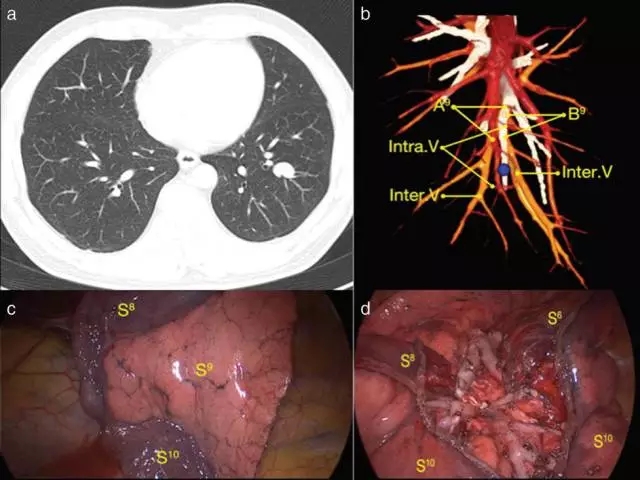

从2013年到2015年,539例结节小于2厘米的非小细胞肺癌病人,接受了全胸腔镜解剖性肺段切除术。术前采用3D-CTBA技术,辨别靶肺段支气管和动脉,以及段内静脉和段间静脉的分布, 明确手术的路径和切除的边界范围,见图a和b。

开刀侧的肺,予以充气张肺,气道压力控制在20厘米水柱,经过5-12分钟,靶段肺完全膨胀,然后改回对侧肺单肺通气,让手术侧的肺气道与大气相通,这时,就能非常清晰地看到“英得福线”,见图c,靶段肺膨胀,其周边正常肺段组织萎陷,产生清晰的分界线。沿“英得福线”和段间静脉分离,至肺野外周三分之一,用腔镜切割吻合器切断靶段与周边肺段间组织,这样可以完整切除“锥形”的靶段肺组织,见图d. 采用这种技术,“英得福线”和肺本身的肺段分界线完全吻合。